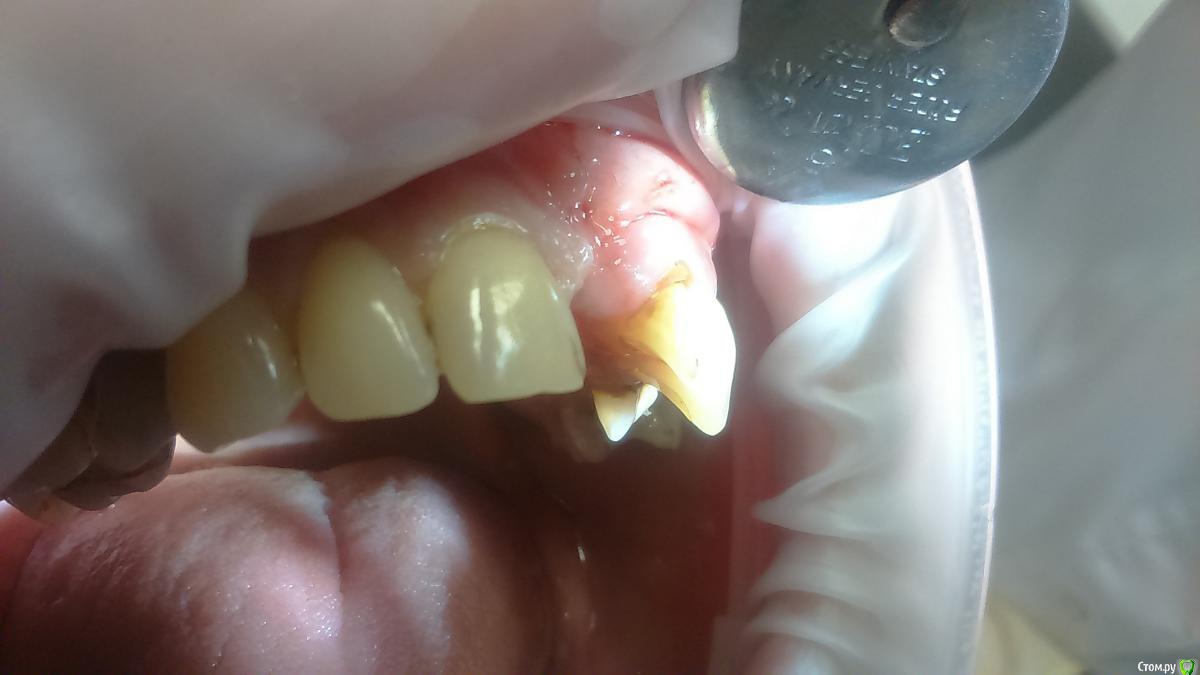

Platon Опубликовано 31 января, 2016 Автор Поделиться Опубликовано 31 января, 2016 Продолжение.не судите строго за фото, первый раз вообще фоткаю операцию)спасибо за советы.По порядку. После того, что мне написали, я решил все -таки уговорить на конусный имплантат (3.7-11.5 ImplantDirect). Также ортопед не хотел делать временную коронку, сказал что сделает каппу, птичку в топку -тоже сделали. Слизистая в области 21 была в рубцах. Исходя из этого всего я решил, коль временной коронки не будет, то сст подсаживать тоже не стану пока,(ортопеда уговаривал сделать временную коронку)))- торк был хороший 35-50н) для того чтобы сст попрактиковаться, но(((.в итоге, анестезия, разрез, сверло пилотное и сверло 2.2, далее расщепление с помощью набора майзенгер с использованием спредеров до нужного диаметра, установил имплантат, торк контролируемый, можно было подобрать любой) в итоге оставил 35. заглушка, совсем немного ксено, мембрана, ушился. ждем. Будет что-то типо каппы которая слегка отдавливает десну,формируя сосочки. не знаю, ни разу такую еще не видел.планирую на этапе раскрытия все-таки сст и временную коронку увидеть.вот. через 4 мес. выложу, что получилось) Если есть советы, критика, всему буду рад, спасибо 3 Ссылка на комментарий